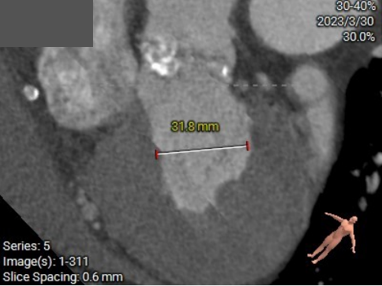

三叶瓣,瓣环偏大,右无瓣叶钙化重;LVOT直径小于瓣环直径,呈漏斗形;窦部直径可,STJ及升主直径偏小,双冠脉高度可;主动脉根部角度约39°;室间隔及室壁增厚,LV偏小。

三叶瓣,瓣叶钙化重,限制区高锚定力可,LVOT上宽下窄有利于密封,预装29型号Evolut PRO瓣膜;